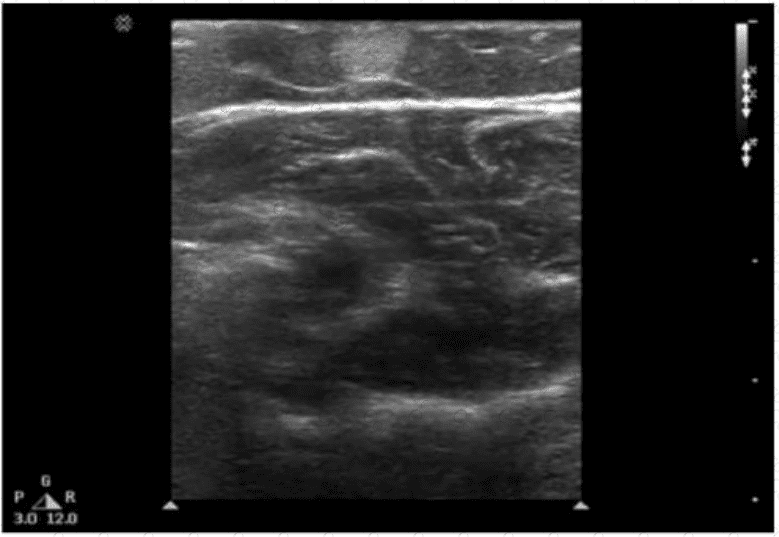

Which condition is most consistent with the sonographic appearance in this image of the abdominal wall?